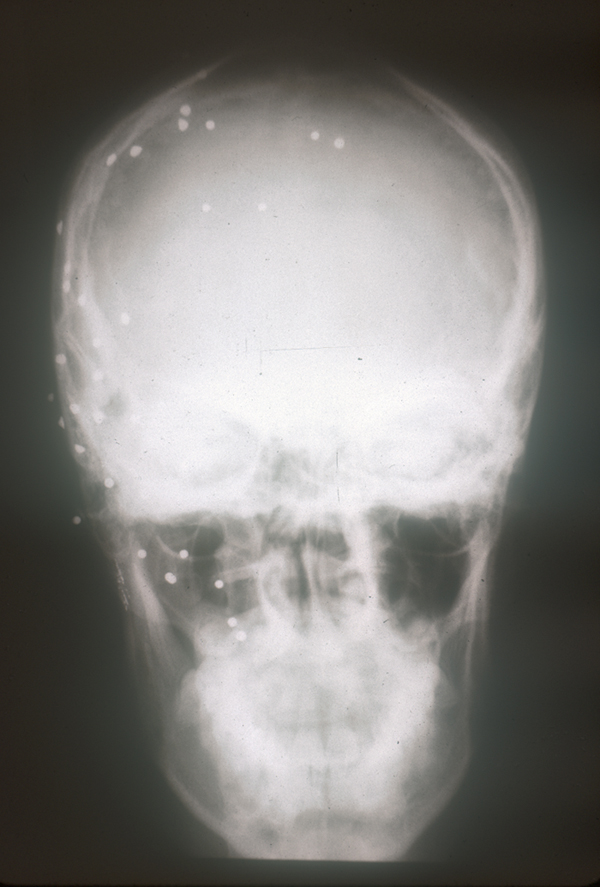

arma_fuego_cabeza2.JPG (229722 bytes)

Herida en cabeza

arma_fuego_cabeza.JPG (280287 bytes)